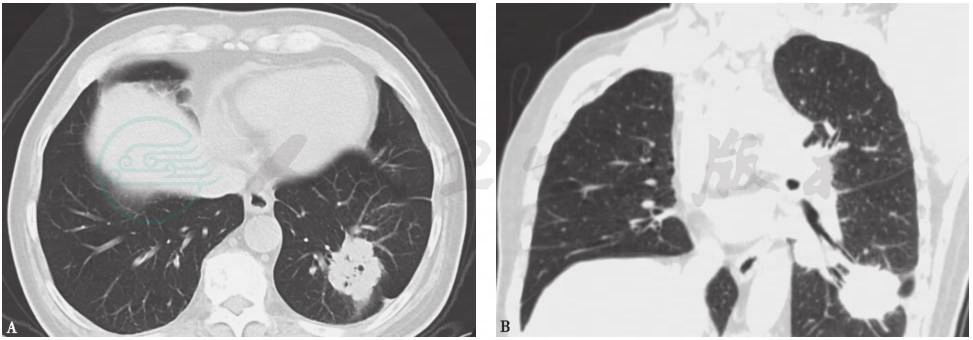

图2 胸部CT表现(2014-05-05)

胸部CT显示左侧少量自发性气胸伴皮下气肿和少量胸腔积液,右肺下叶团块状影